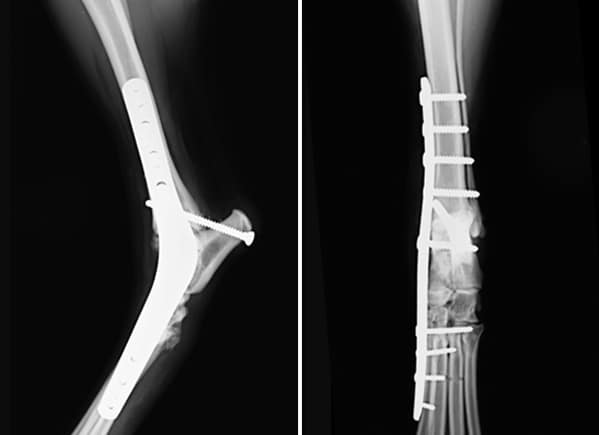

Pancarpal/Pantarsal Arthrodesis

A complete arthrodesis involves fusion of the entire joint, eliminating all range of motion. A complete arthrodesis is necessary when the tibiotarsal or radiocarpal joints are affected. The cartilage is removed between all joints within the wrist or ankle then filled with bone graft. A specialized bone plate and screws are used to stabilize the bones until they fuse completely.

Arthrodesis is a salvage procedure where the affected joint is fused, either partially or completely depending on the site of injury. Arthrodesis is reserved for when reconstruction fails or severe injuries to other structures limits our ability to adequately reconstruct. Cartilage is removed from all affected joints. The joints are packed with bone graft then the bones are secured with a bone plate and screws while they fuse. The repair will need to be protected for 8 weeks with a splinted bandage. X-rays are rechecked at 8 and 12 weeks to assess fusion. Activity is restricted for 12-16 weeks to allow complete fusion.